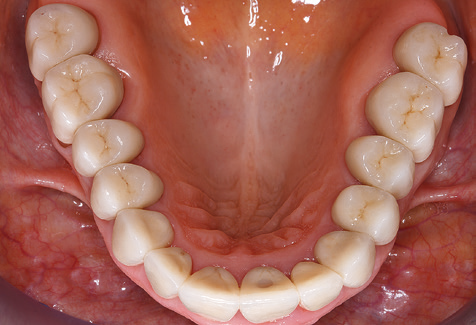

A 52-year-old patient presented in our clinic for the first time in 2004 following tooth loss in the third quadrant, expressing a desire for a new prosthetic restoration. Periodontal and radiological diagnostics revealed the need for extensive periodontological treatment. In addition, teeth 48, 28 and 27 were attributed a very poor prognosis and were subsequently extracted (Fig. 1). Following the successfully completed, systematic periodontological treatment, a fixed dental implant was inserted with the introduction of five implants in tooth regions 35, 36, 37, 46 and 47. Prosthetic treatment of the natural teeth was effected with veneered zirconium dioxide ceramic crowns; the implants were composed of two-piece, individual zirconium dioxide abutments and similarly veneered crowns made of a zirconium dioxide ceramic (Cercon base colored, Dentsply Sirona Lab). Definitive insertion of the prosthetic restoration occurred in 2005.

Due to the presence of periodontal disease, SPT was performed every three months in the first years following the insertion. The patient demonstrated a high degree of motivation and good compliance. The pocket depths recorded annually revealed a stable periodontal situation with a BOP index of below five per cent. On the basis of the stable periodontal situation and good cooperation on the patient’s part, the recall interval was extended to every six months as of the sixth year of the prosthetic function phase. Following the change in the recall interval, the respective annual documentation of the periodontal status continued to reveal a stable periodontal situation with no increase in the pocket depths and a BOP index below five per cent (Fig. 2a and b).